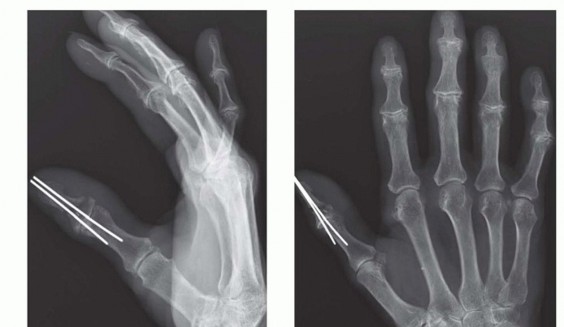

A survival rate greater than 80% is expected for replantation surgery.Functional outcomes are greatest for replantation of the thumb, proximal hand, and single digit distal to the FDS insertion (FIG 6A-D).5,6,13,16Recovery of sensation is correlated with function. As in other peripheral nerve injuries, age is the most important factor for recovery, with better results in younger patients. The average two-point discrimination inreplanted thumbs is 11 mm and in fingers is 8 mm.4 These values represent the average recovery for sharp amputation. Crush and avulsion mechanisms result in poorer two-point discrimination.Range of motion is related to level of amputation. Active PIP joint motion in replantations proximal to the FDS insertion average 35 degrees, whereas replantations distal to the FDS insertion result in 82 degrees of PIPjoint motion (FIG 6E-G).7

FIG 6 • A-D. This patient sustained an amputated thumb, which was successfully replanted with good cosmetic and functional results. E-G. Successful replantation of the ring and small fingers resulted in a functional hand capable of holding common objects. Vigilant reexamination of color, warmth, turgor, and capillary refill is necessary to decide whether exploration in the operating room is indicated. Revisions after 4 to 6 hours of reduced perfusionseldom result in digit salvage.7If venous engorgement occurs postoperatively, elevate the hand and remove constrictive dressings (including sutures that are too tight).Consideration for return to the operating room is based on intraoperative findings affecting the possibility of revising the venous anastomosis.If this is not possible, leeches or nail removal are used to alleviate venous congestion. These methods typically are used to bridge the first 4 to 6 days until adequate outflow is established.